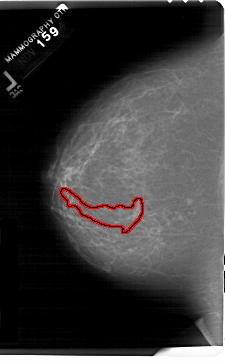

A_1202_1.LEFT_CC

FILE: A_1202_1.LEFT_CC.OVERLAY

TOTAL_ABNORMALITIES 1

ABNORMALITY 1

LESION_TYPE CALCIFICATION TYPE PLEOMORPHIC DISTRIBUTION SEGMENTAL

ASSESSMENT 5

SUBTLETY 3

PATHOLOGY MALIGNANT

TOTAL_OUTLINES 1

BOUNDARY